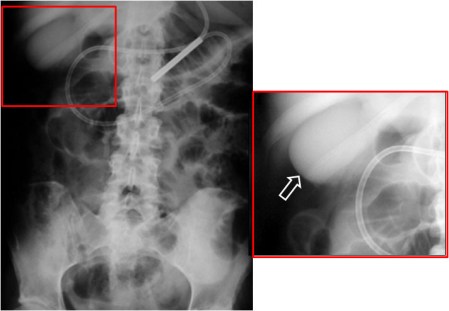

SIGNO DE LA DOBLE PARED O SIGNO DE RIGLER

En la radiografía simple de abdomen, la presencia de aire a ambos lados de la pared gástrica o intestinal, indica la existencia de neumoperitoneo.

La detección de este signo es importante en pacientes que, por su estado, no pueden adoptar la posición erecta o el decúbito lateral. Se ha descrito una imagen similar cuando se yuxtaponen dos asas intestinales distendidas, en pacientes sin neumoperitoneo.

Este signo puede verse también en la radiografía de tórax (1), en la TC (2), y en la placa de abdomen en decúbito supino con rayo horizontal (3) aunque, en general, se requieren cantidades mayores de neumoperitoneo para su demostración.